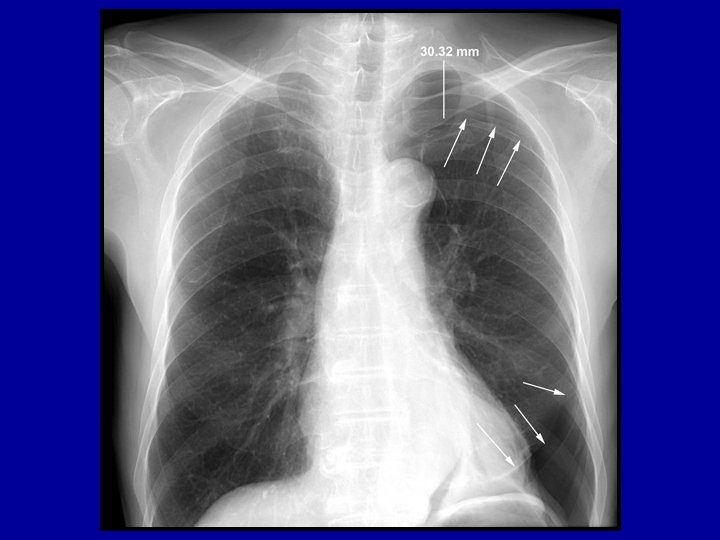

Case Study #2 22 year old man was admitted five days ago after an MVC. He sustained a left rib fractures, a left pneumothorax and a left femur fracture. The nurse states the patient is short of breath. His temp is 37. 1 o, his HR is 95, RR 30 and BP 120/70. His saturation on room air is 85%

Differential Diagnosis • • Pneumothorax Pneumonia Lobar collapse Pulmonary embolus

Case study #2 • When the situation is not life threatening there is ample time to perform the necessary diagnostic tests and manuevers • In a life threatening situation immediate action is necessary to prevent arrest • For example, if you suspect someone has a tension pneumothorax as a life saving manuever you should perform needle decompression with a 14 gauge angiocath rather than wait for a tube thoracostomy and scalpel, etc.